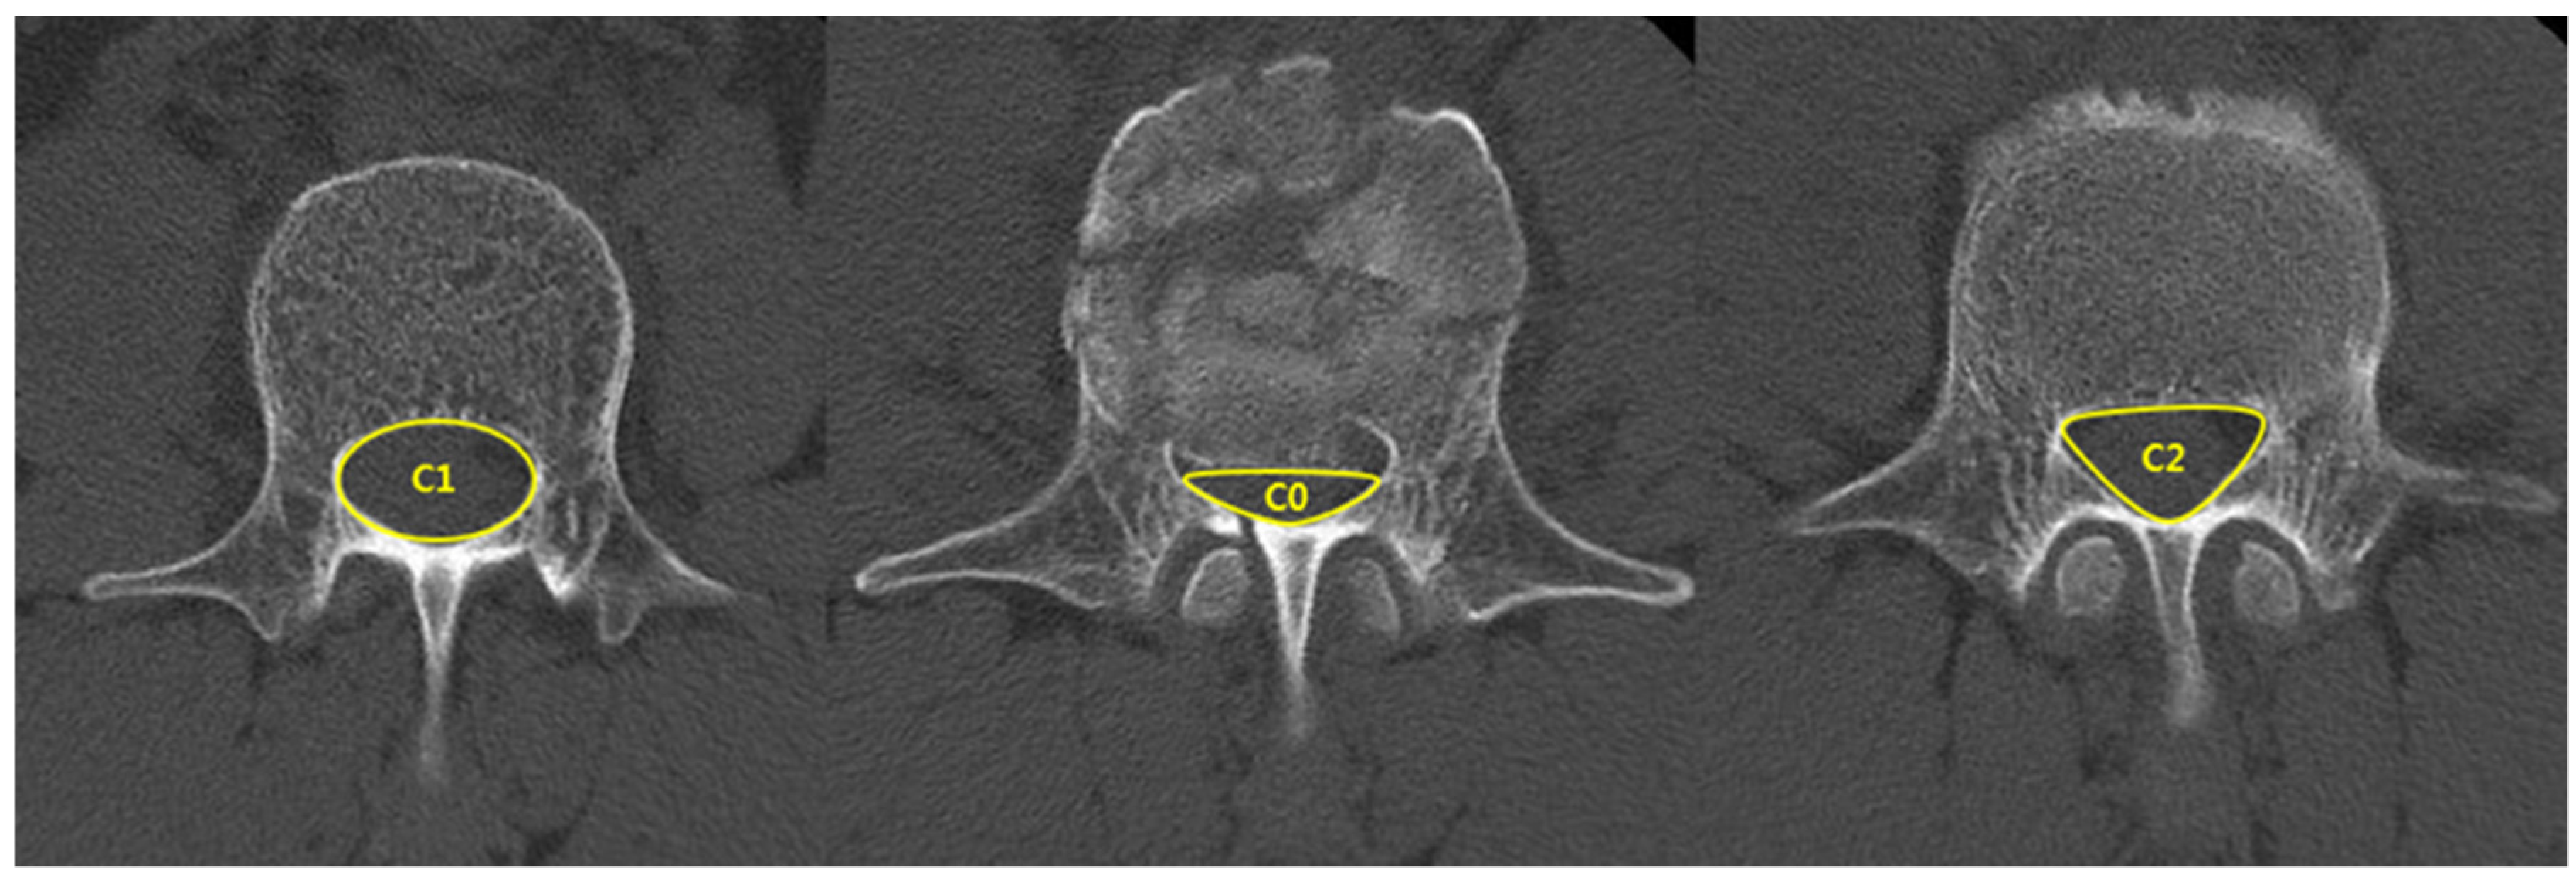

| Spinal canal compromise (%) ‡ | 27.9 ± 7.6 | 35.7 ± 13.3 | 0.03 |

| Loss of vertebral body height (%) ‡ | 28.6 ± 7.8 | 34.1 ± 6.0 | 0.01 |

| Kyphotic angle (°) ‡ | 10.1 ± 6.2 | 13.9 ± 5.0 | 0.04 |